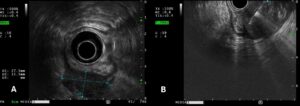

Endoscopic ultrasound confirmed the presence of a well circumscribed homogeneous hypoechoic lesion, with well-defined borders, measuring approximately 34 x 30 mm, arising from the muscular layer. Fine-needle biopsy using a 22-gauge needle was performed (figure 2).

Figure 2: (A) EUS shows a homogeneous hypoechoic lesion, with well-defined borders (34×30 mm), arising from the muscular layer; (B) Tissue sampling was performed using 22-gauge fine needle biopsy (FNB).